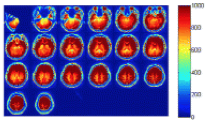

Arterial Spin Labeling (ASL) is an emerging magnetic resonance imaging technique attracting increasing attention in dementia diagnosis only beginning from recent years. ASL is capable to provide direct and quantitative measurement of cerebral blood flow (CBF) of scanned patients, so that brain atrophy of demented patients could be revealed by measured low CBF within certain brain regions through ASL. However, partial volume effects (PVE) mainly caused by signal cross-contamination due to pixel heterogeneity and limited spatial resolution of ASL, often prevents CBF from being precisely measured. Inaccurate CBF is prone to mislead and even deteriorate dementia disease diagnosis results, thereafter. In this paper, a novel dementia disease diagnosis strategy based on ASL is proposed for the first time. The diagnosis strategy is composed of two steps: 1) to conduct pixel-wise PVE correction on original ASL images and 2) to predict dementia disease severities based on corrected ASL images via ranking. Extensive experiments and comprehensive statistical analysis are carried out to demonstrate the superiority of the new strategy with comparison to several existing ones. Promising results are reported from the statistical point of view.